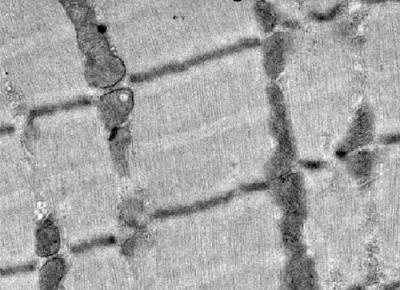

A heart muscle protein can replace its missing skeletal muscle counterpart to give mice with myopathy a long and active life, show Nowak et al. The findings will be published online on Monday, May 25, 2009 ( www.jcb.org ) and will appear in the June 1, 2009 print issue of the Journal of Cell Biology .

The contraction machinery protein, actin, exists in different forms in the adult heart and skeletal muscles. The heart form, ACTC, is also the dominant form in skeletal muscle of the fetus. But during development, the skeletal form, ACTA1, increases in production and by birth has taken over. It is not clear why the switch occurs, or why it doesn't occur in the heart, but it happens in every higher vertebrate and, for that reason, has been considered vitally important.

But it did. Nowak and colleagues crossed Acta1 mutant mice with transgenic mice that express human ACTC at high levels in skeletal muscle cells. The resulting mice didn't die at nine days. In fact, almost all of them (93.5%) survived more than three months, and some more than two years. The mice's locomotor performance was comparable with wild-type, as was their overall muscle strength (though individual muscle fibers were slightly weaker), and their endurance was actually higher—they ran faster and for longer.